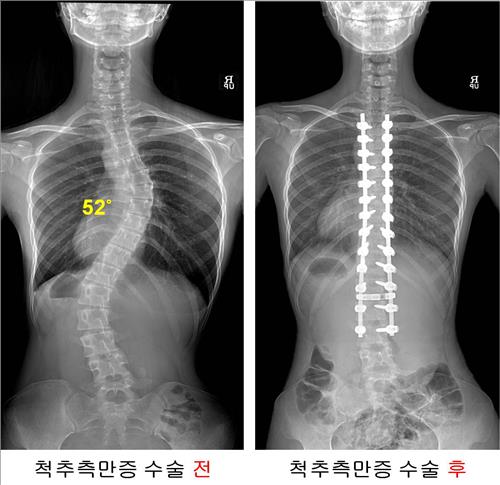

"ôÃßÃø¸¸Áõ ¼ö¼úȯÀÚ 85%°¡ 10´ë ¿©Çлý"